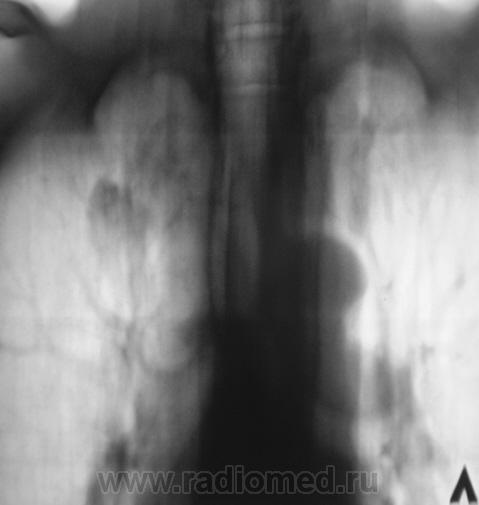

Плотные очаги на измененном легочном фоне.Связь с корнем легкого.А туберкуломы или нет- трудно сказать.Я присоединюсь к посту Сан Саныча 1 о томограммах.Валентин Львович,не томите душу.

Тень локализуется на " своем " типичном месте,имеет типичный размер, контуры ее относительно четкие ровные,наличие полостей распада, одна у нижнего полюса ,видна полоска дренирующего бронха.Мое мнение, что это туберкулома.+ характерные изменения верхней доли левого легкого.

Туберкулома с характерным распадом.

Я за тбц. То есть за туберкулому.

Стоит на учете, но вот ранее туберкуломы не было.

МБТ, тоже, со временем, были обнаружены.